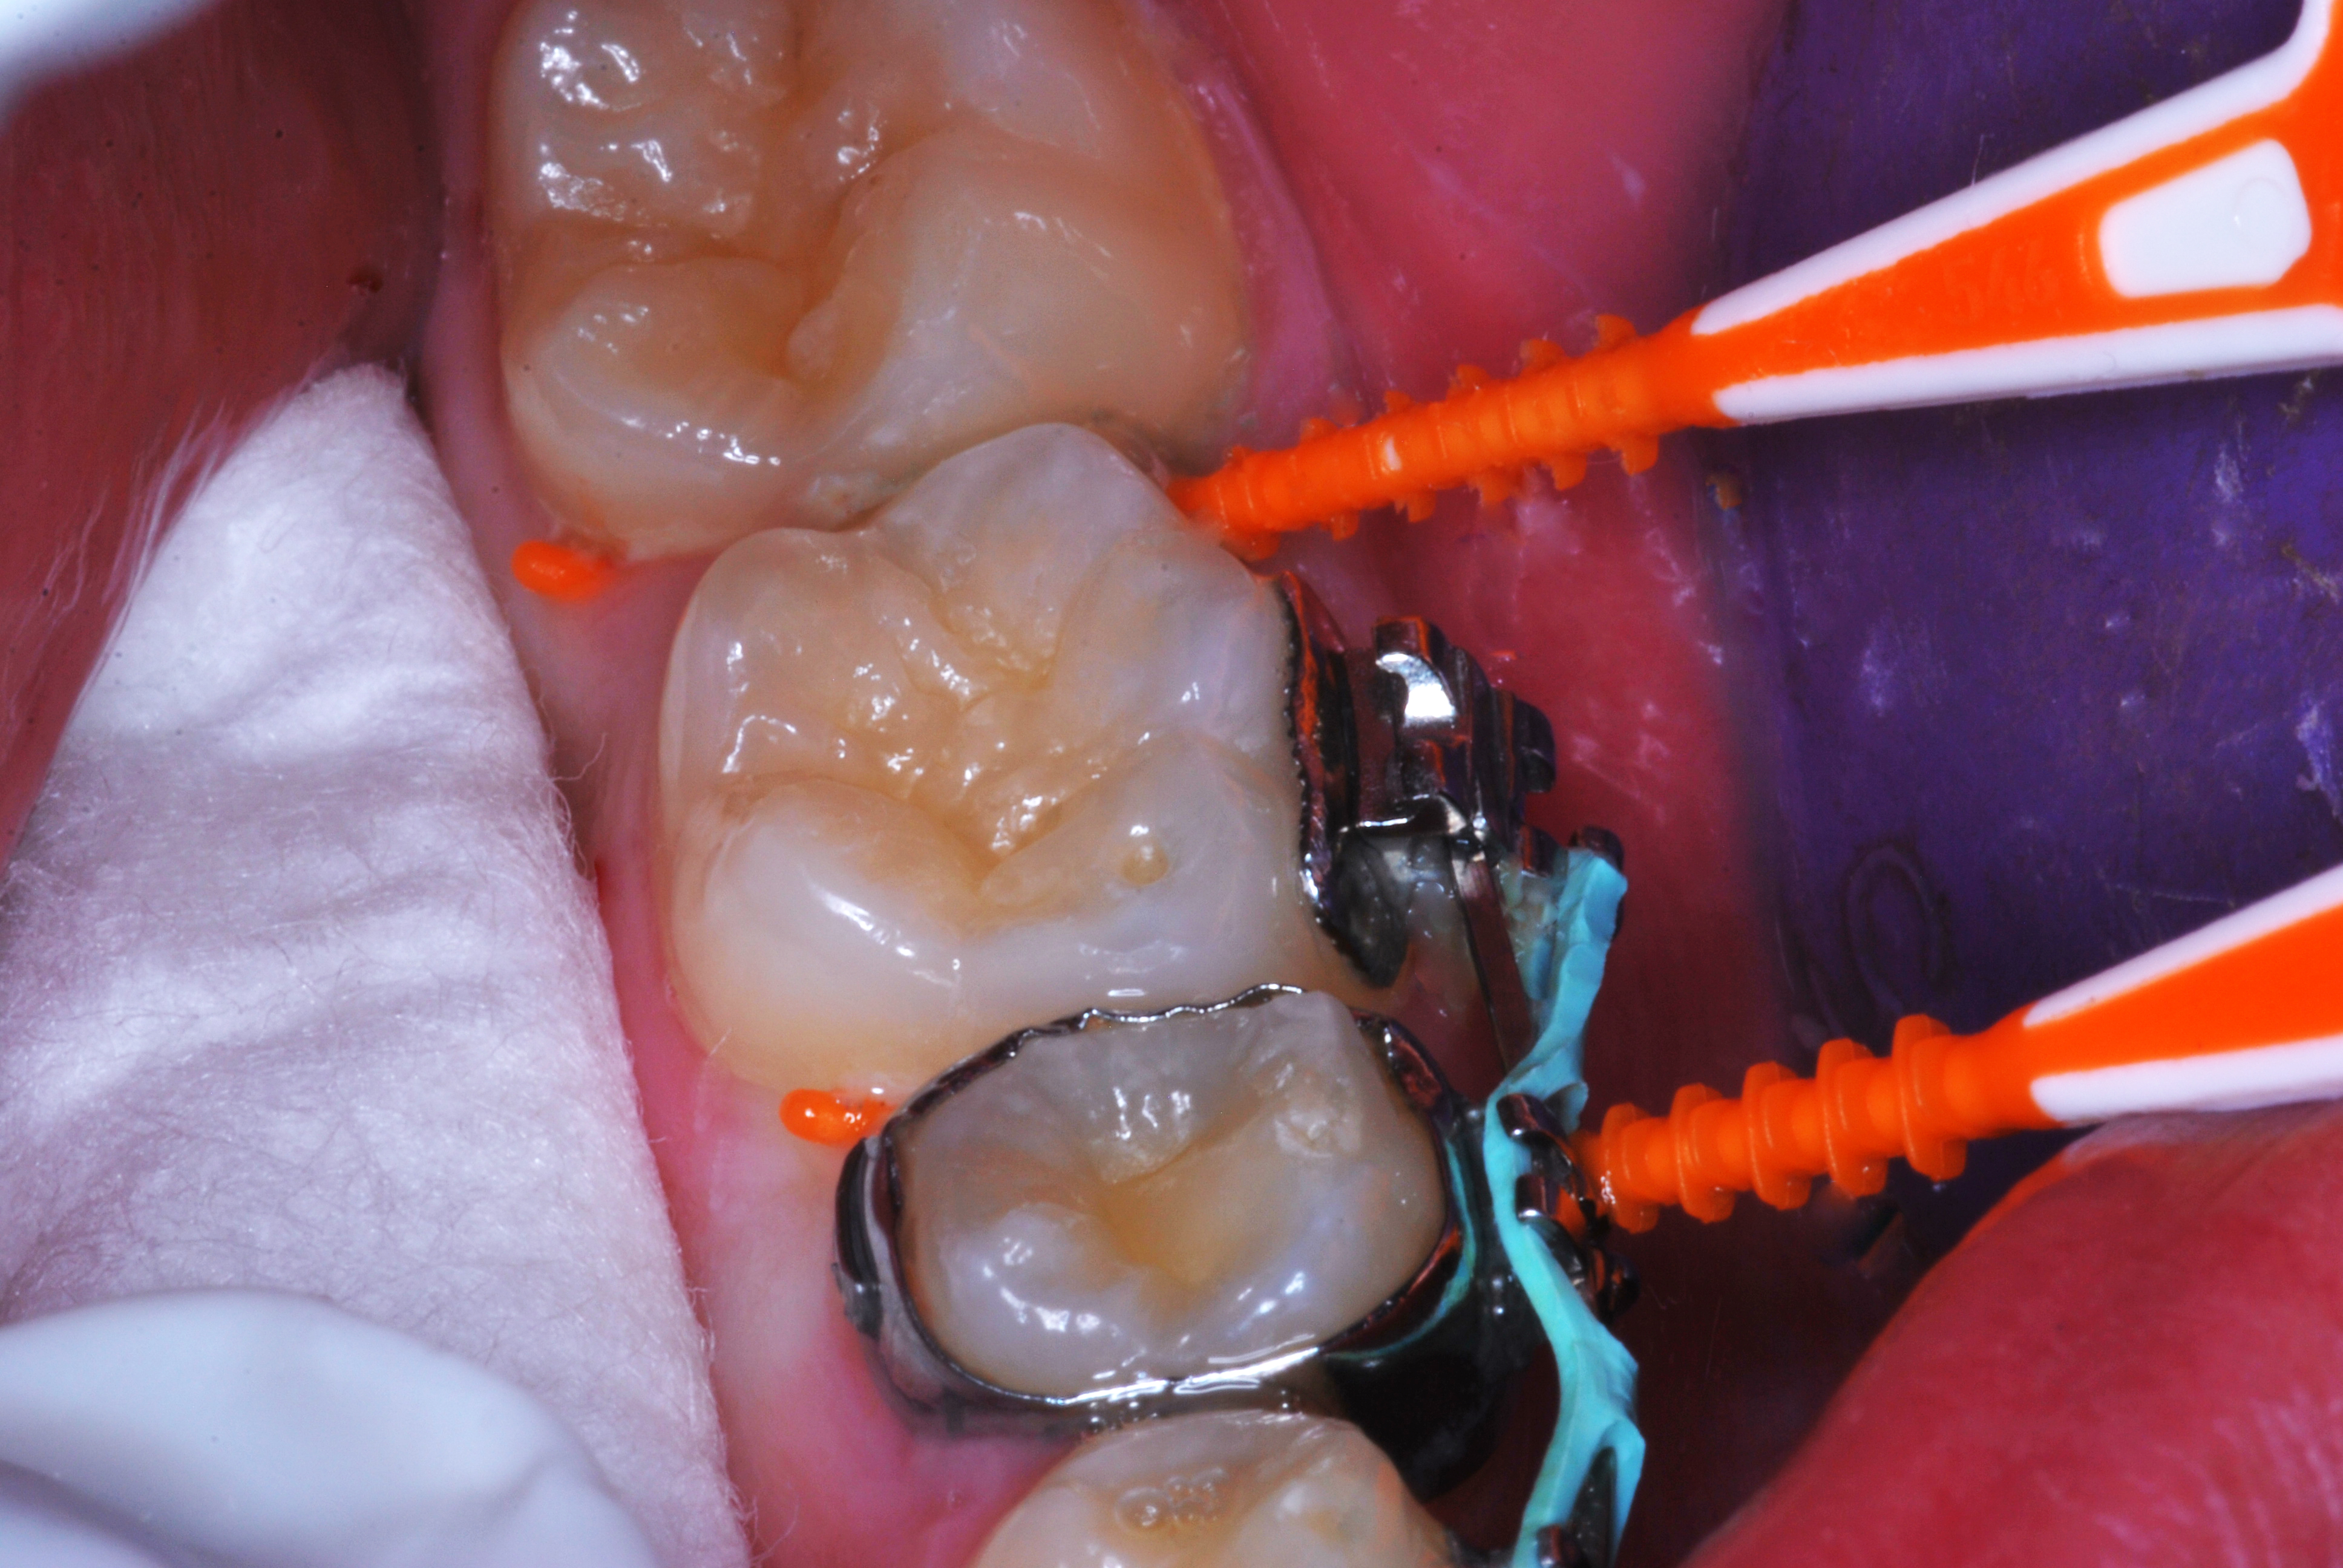

(26.) Silver modified atraumatic restorative technique (SMART) caries control treatment demonstrated on extracted carious primary molar.

Figure 26

(27.) Silver modified atraumatic restorative technique (SMART) caries control treatment demonstrated on extracted carious primary molar.

Figure 27

(28.) Silver modified atraumatic restorative technique (SMART) caries control treatment demonstrated on extracted carious primary molar.

Figure 28

(29.) Silver modified atraumatic restorative technique (SMART) caries control treatment demonstrated on extracted carious primary molar.

Figure 29

30.) Silver modified atraumatic restorative technique (SMART) caries control treatment demonstrated on extracted carious primary molar.

Figure 30

(31.) Silver modified atraumatic restorative technique (SMART) caries control treatment demonstrated on extracted carious primary molar.

Figure 31

(32.) Silver modified atraumatic restorative technique (SMART) caries control treatment demonstrated on extracted carious primary molar.

Figure 32